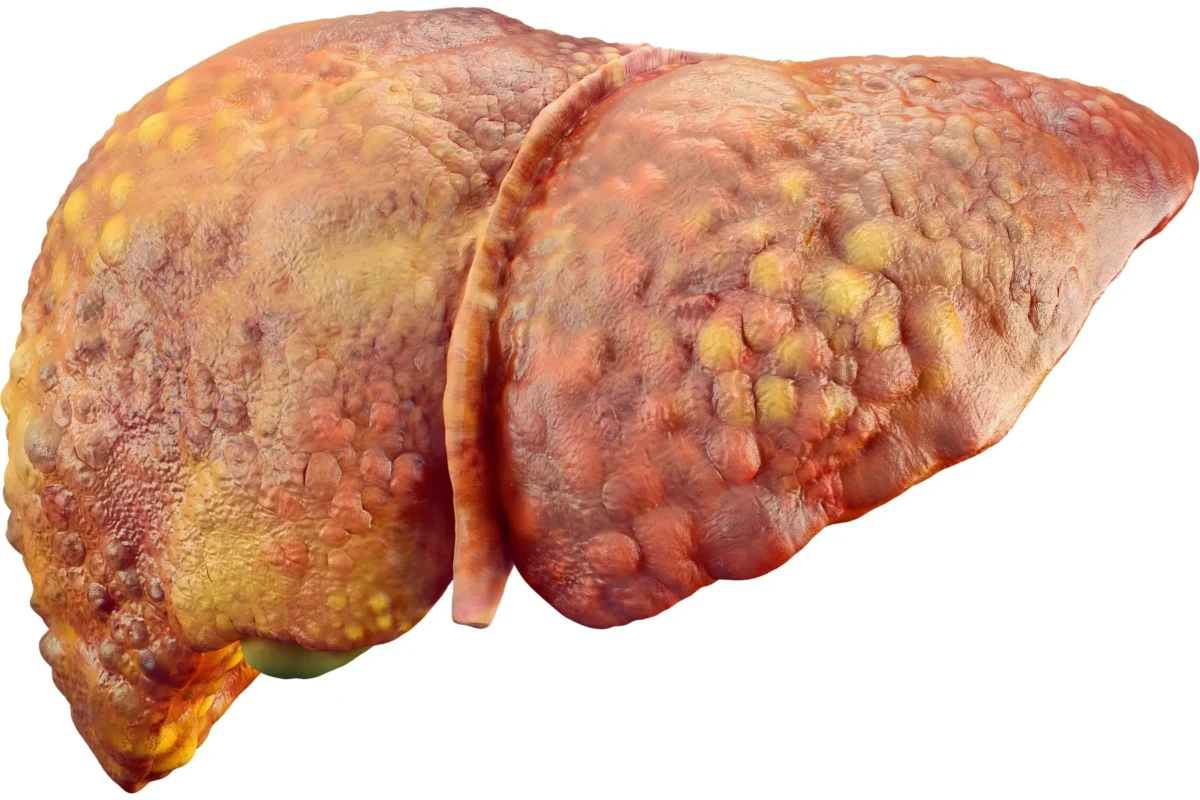

Whether you’re managing Non-Alcoholic Fatty Liver Disease (NAFLD) or trying to improve liver enzyme levels, a balanced, scientifically designed diet is key to recovery.